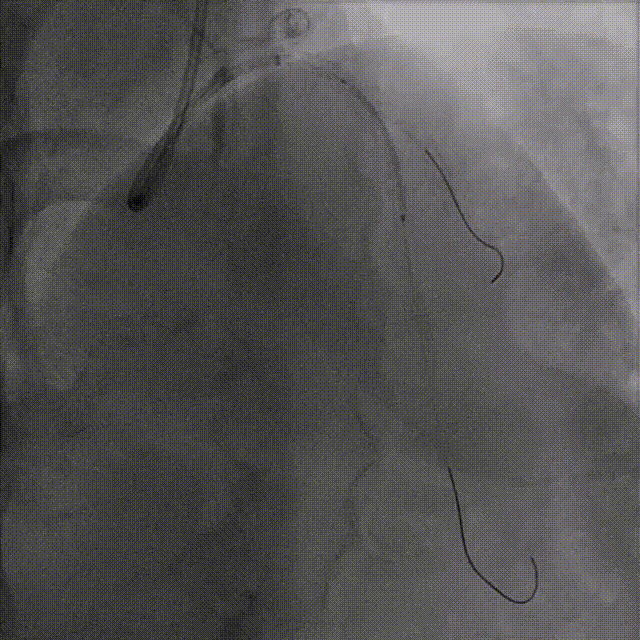

IVUS实时定位寻找开口

沿7F UBS3.5送Runthrough导丝至D1,

LAD开口不明确,送入IVUS至D1手动回撤,实时寻找LAD开口方向